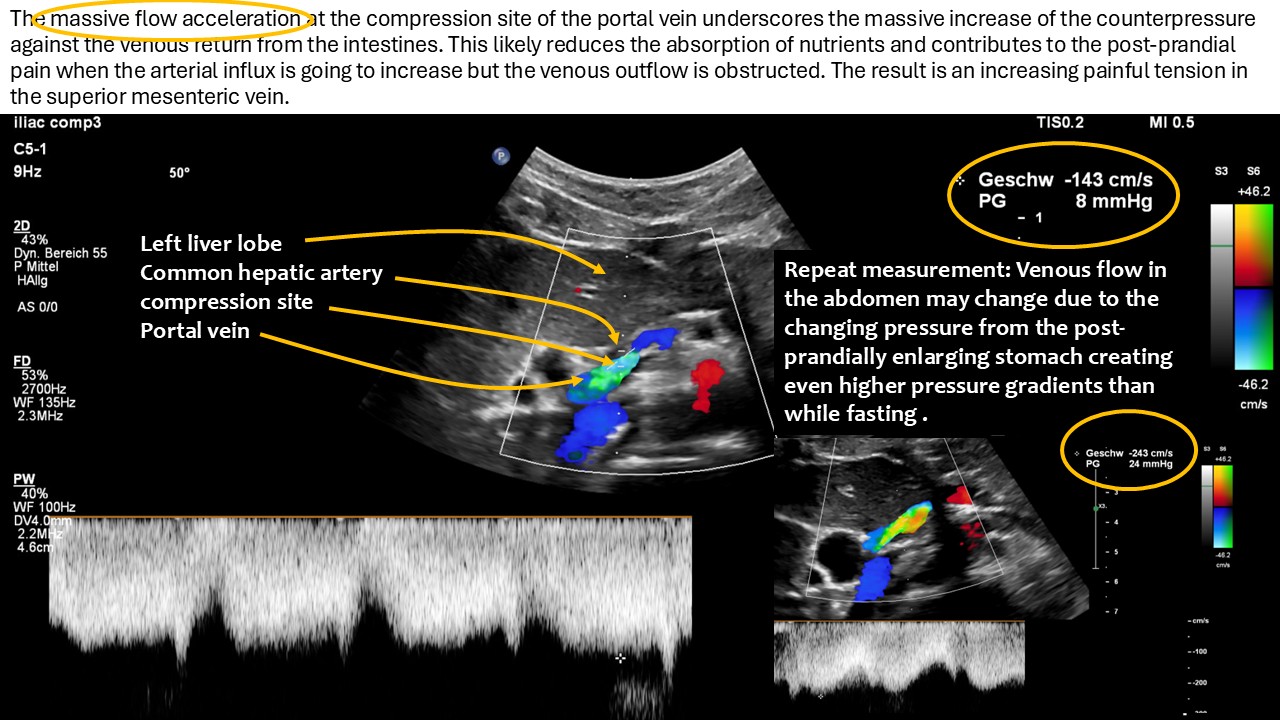

Since the common hepatic artery compressed the portal vein significantly with a flow acceleration to 147 cm/s the pressure within the splenic vein was completely transferred onto the venous return from the small bowel via the superior mesentric vein.

- Severe compression of the portal vein by the common hepatic artery reducing the venous outflow from the small intestines and thus contributes to the maldigestion and malabsorption of the patient

The superior mesenteric vein and the splenic vein converge to form the portal vein. This vessel is typically of a relatively short length, given that the confluence of the superior mesenteric and splenic veins occurs in close proximity to the liver in most individuals. However, in this particular case, the portal vein exhibited a notable elongation, a consequence of the left-sided unification of the superior mesenteric and splenic veins. This anatomical variation potentially renders the portal vein more vulnerable to dislocation, making subsequent compression by the common hepatic artery easier. It should be noted that similar cases have been previously documented on this website, albeit in the absence of malrotation. In these cases, the compression was precisely at the point of unification between the two veins, namely the superior mesenteric and splenic veins. This may have resulted in a residual bypass from the superior mesenteric vein to the portal vein, thereby leading to a subtotal compression of the superior mesenteric vein.

All In this instance, the circumstances were somewhat divergent. The portal vein was of a greater length due to the unification of the splenic and superior mesenteric veins being in close proximity to the spleen. Consequently, there was a complete transfer of pressure from the compression site at the portal vein to both of these veins.

I have previously outlined the impact on the venous return from the small bowel with a 4D-PixelFlux volume flow measurement of the superior mesenteric vein and artery.

This showed that blood flow to the small bowel was reduced, probably because of the blockage. Moreover, this situation implies increased pressure in the superior mesenteric vein which was much wider than the accompanying superior mesenteric artery as a sign of the painful distension. An increase in intra-abdominal pressure, whether it occurs orally or via a feeding tube, can result in the onset of acute pain due to the subsequent rise in pressure within the mesenteric and renal veins on the left side of the body. This phenomenon is further compounded by the obstruction of venous outflow from the spleen, which can exacerbate discomfort in the region below the left rib cage.